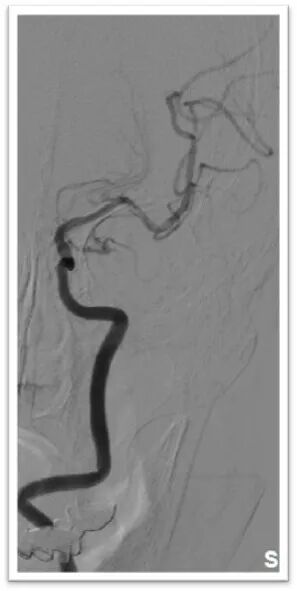

微导丝引导微导管顺利置于左侧大脑中动脉上干,半释放6-30mm支架,停留5分钟后完全取出血栓,造影显示左侧大脑中动脉血流完全恢复,mTICI:3级。

术后即刻造影结果